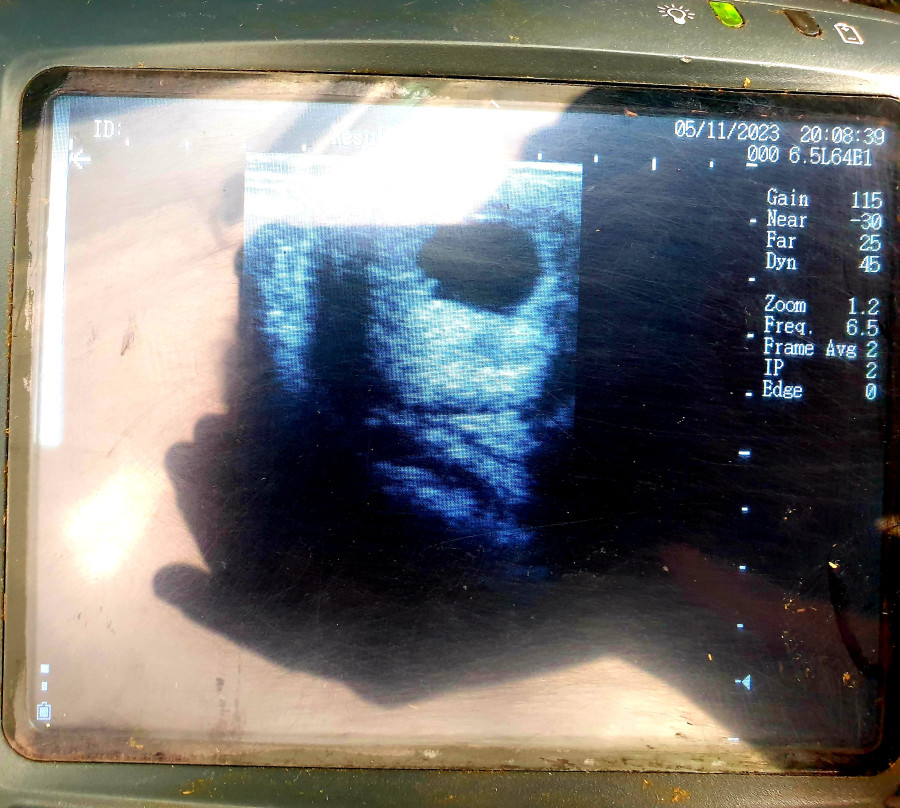

Écho aujourd'hui pour vérifier le DG de lundi (suspicion de jumeaux) : Elle est a 17/18j, et il n'y en a qu'un !

Ca nous donne un début de terme le 7 mars, on verra si elle nous fait le même coup que l'an dernier (elle a attendu 354j), mais dans l'idée bébé O devrait arriver mi/fin mars